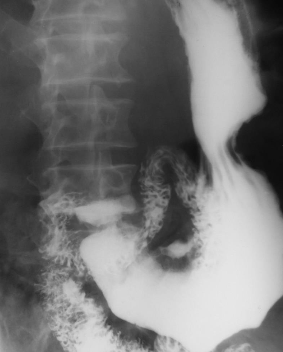

Hernie hiatală

Hernie hiatală prin alunecare

Hernie hiatală prin rostogolire

Hernie hiatală - brahiesofag

Volvulus gastric